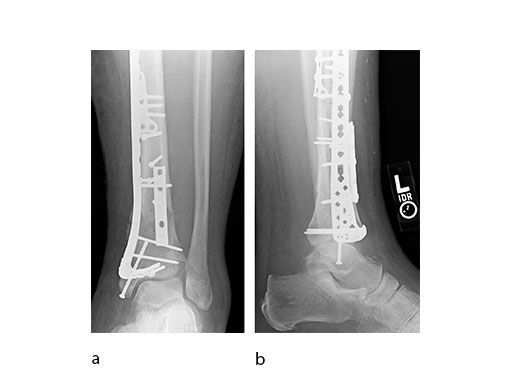

A 45-year-old patient fell from his horse, receiving a closed bimalleolar fracture/ dislocation (Fig 10). Computed tomorgraphy demonstrated an additional anterolateral avulsion injury and syndesmosis dislocation. Osteosynthesis was conducted with a VA-LCP Lateral Distal Fibula Plate.

Push technique was required to achieve fibular reduction, and the syndesmosis was reduced and clamped with periarticular clamps (Fig 11). Postoperative x-rays at 4 weeks demonstrated good maintenance of reduction (Fig 12).